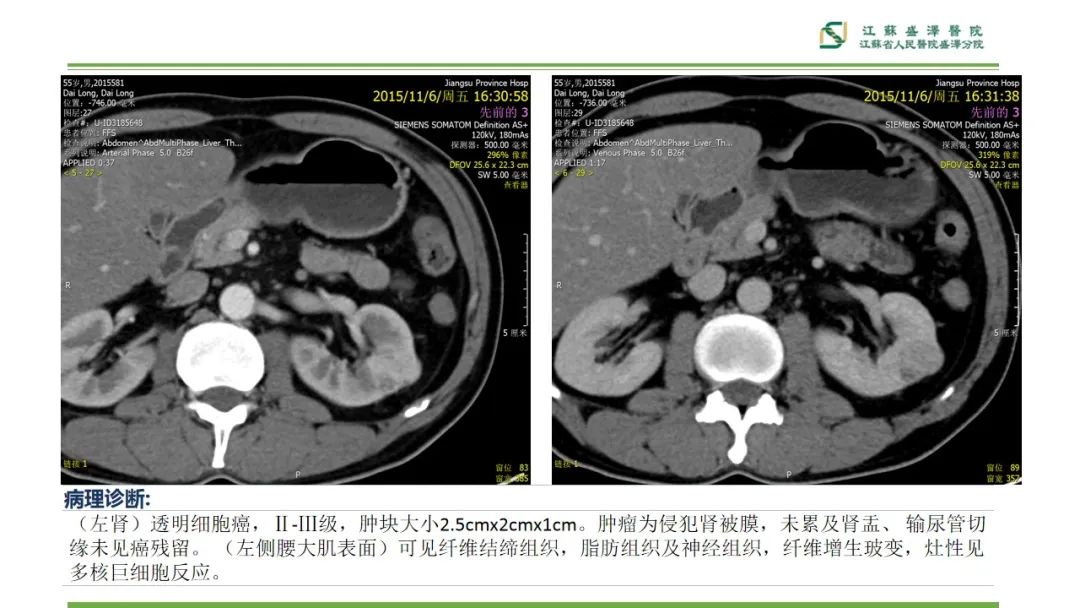

【PPT】肾脏实性肿瘤的良恶性鉴别--影像诊断思路分析-6